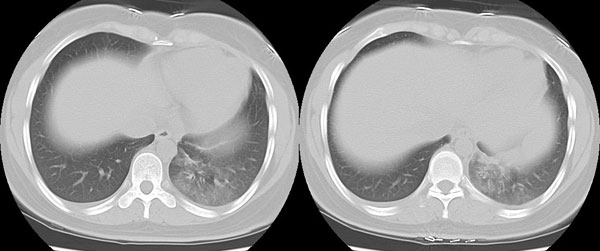

女性,25岁。反复咯血3年,再咯10天。外院x线胸片示:肺炎?支扩?

ct所见:左肺下叶基底段见大片状毛玻璃样改变,其内可见扩张细支气管。

诊断意见:左肺下叶大片状毛玻璃样淡薄影考虑支气管扩张伴出血。

诊断意见:左肺下叶支气管扩张伴出血。

这样的图片能确定是支扩么。看不清啊,要是肺挫裂伤呢

我觉得是出血,感染和出血密度不点不同,请大家注意观察,发些图片上来,一起讨论